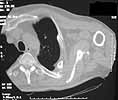

61 yo male 5 months post motorcycle crash. He had "floating shoulder" & flail chest. Pulmonary problems prevented any early intervention. He now has quite severe pain with scapular motion. Would appreciate thoughts on dealing with this. I don't think clavicular osteotomy and restoration of clavicular length will help. His pain seems to be coming from the area where his scapula crosses the significantly deformed ribs.

Can preop planning be assisted by actual 3D models produced by stereolithography or other rapid prototyping techniques reported by Brown et al - OTA 2002. ??